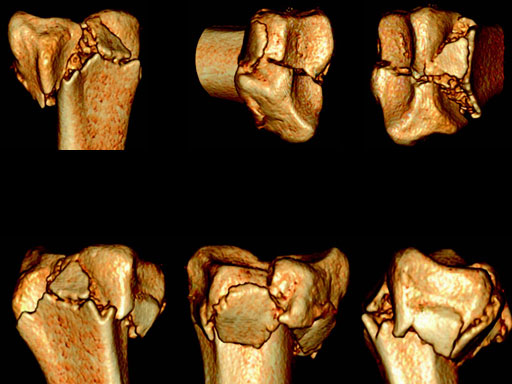

Case 1: 22-year-old male fell off a horse while playing polo.

Case provided by Ladislav Nagy, Zrich, CH

Fig 2af Preoperative 3-D CT scans.